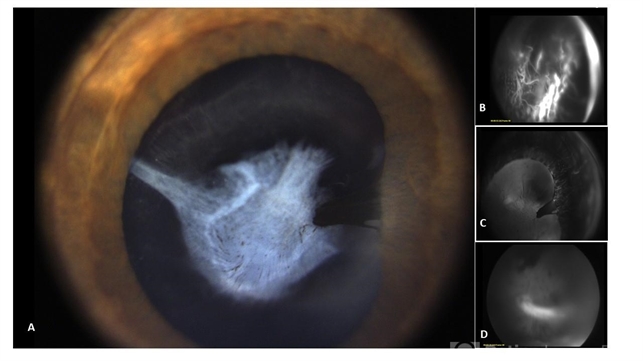

- A 3-year-old male with persistent fetal vasculature and tractional retinal detachment. A: color photograph showing the vascular stalk behind the lens. B: early fluorescein angiogram at 53sec. C: fluorescein angiogram at 2min with focus on the iris D: fluorescein angiogram at 3 min 26sec.